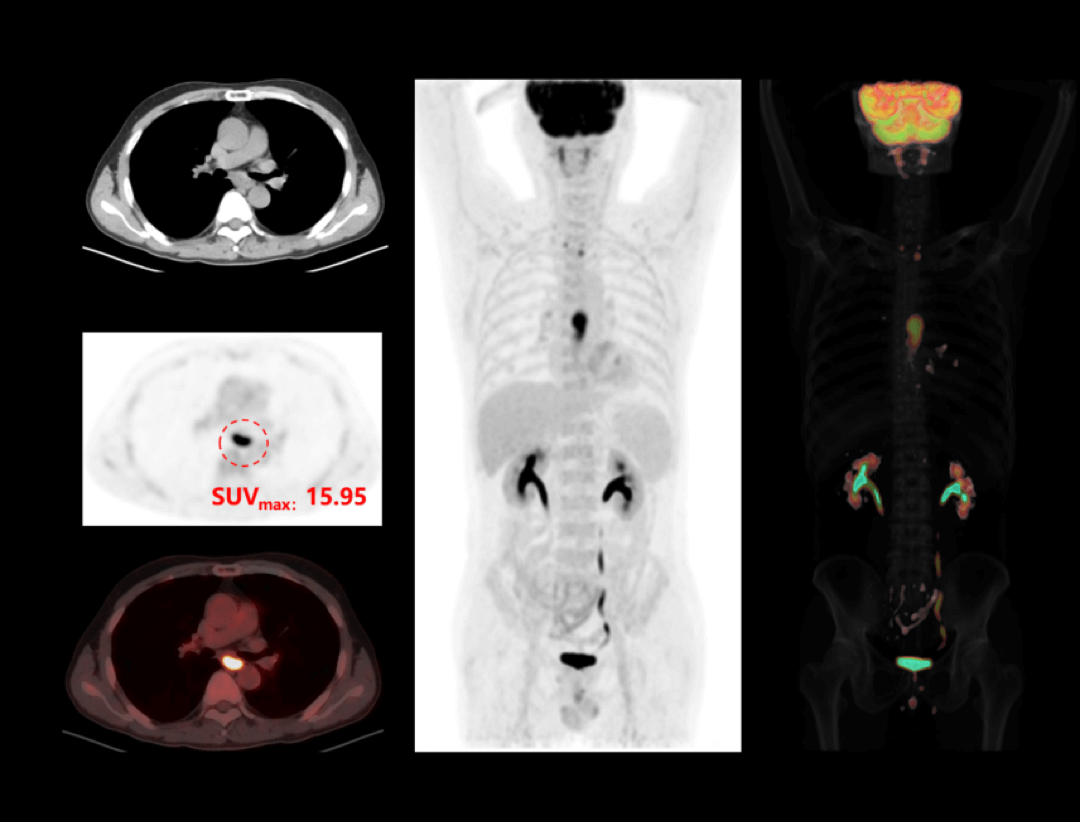

uMI 550搭载自主研发的新一代数字光导探测器,引领PET从「模拟化 」到「数字化 」的时代跨越,系统性能实现多重突破,以超低剂量实现高清成像,大幅提升病灶探测能力;全智能工作流,让临床诊断更精准、更高效、更关爱。

双低剂量,精准影像